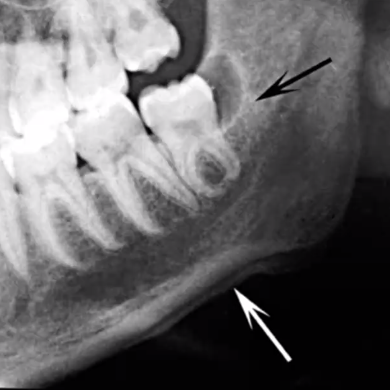

periosteal reaction

reactive process in which new bone is deposited within periosteum for bone expansion

consider osteomyelitis, osteosarcoma (cancer), langerhans cell histiocytosis (cancer)

fistula

path of drainage for pus (neutrophils)

referred as sinus tract, fistulous tract, abscess

can have presence of periosteal reaction